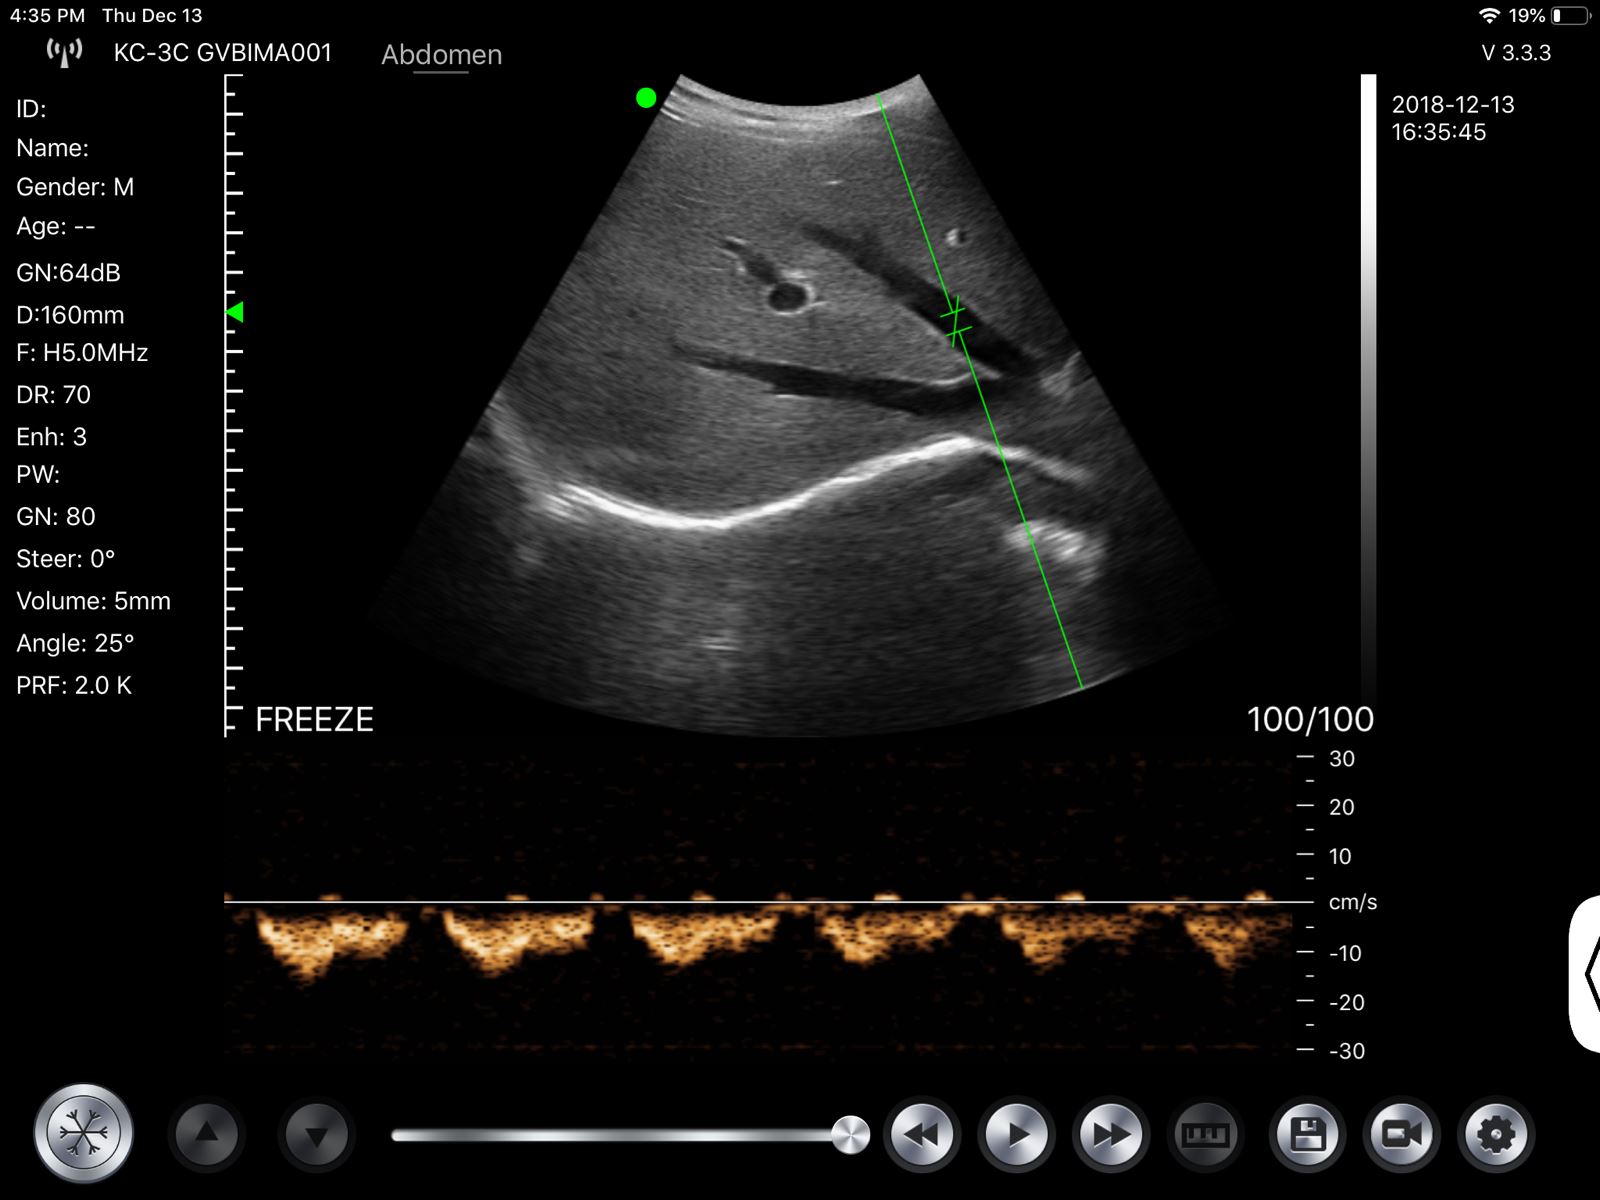

Wireless Fetal Doppler Convex Probe Veterinary Ultrasound for iPad, iPhone App

Wireless Wifi Doppler Convex Array Probe Type Ultrasound Scanner. This wireless Wifi Convex Array Probe with integrated ultrasound circuit boards inside, then realize the functions of an ultrasound scanner. It can be used at many occasions such as In emergency, clinical, and hospital. In addition, CT is easy to operate because it has a unique design with three buttons which is a portable ultrasound machine.

- Display Mode: B, B/M, Color, PW, PDI